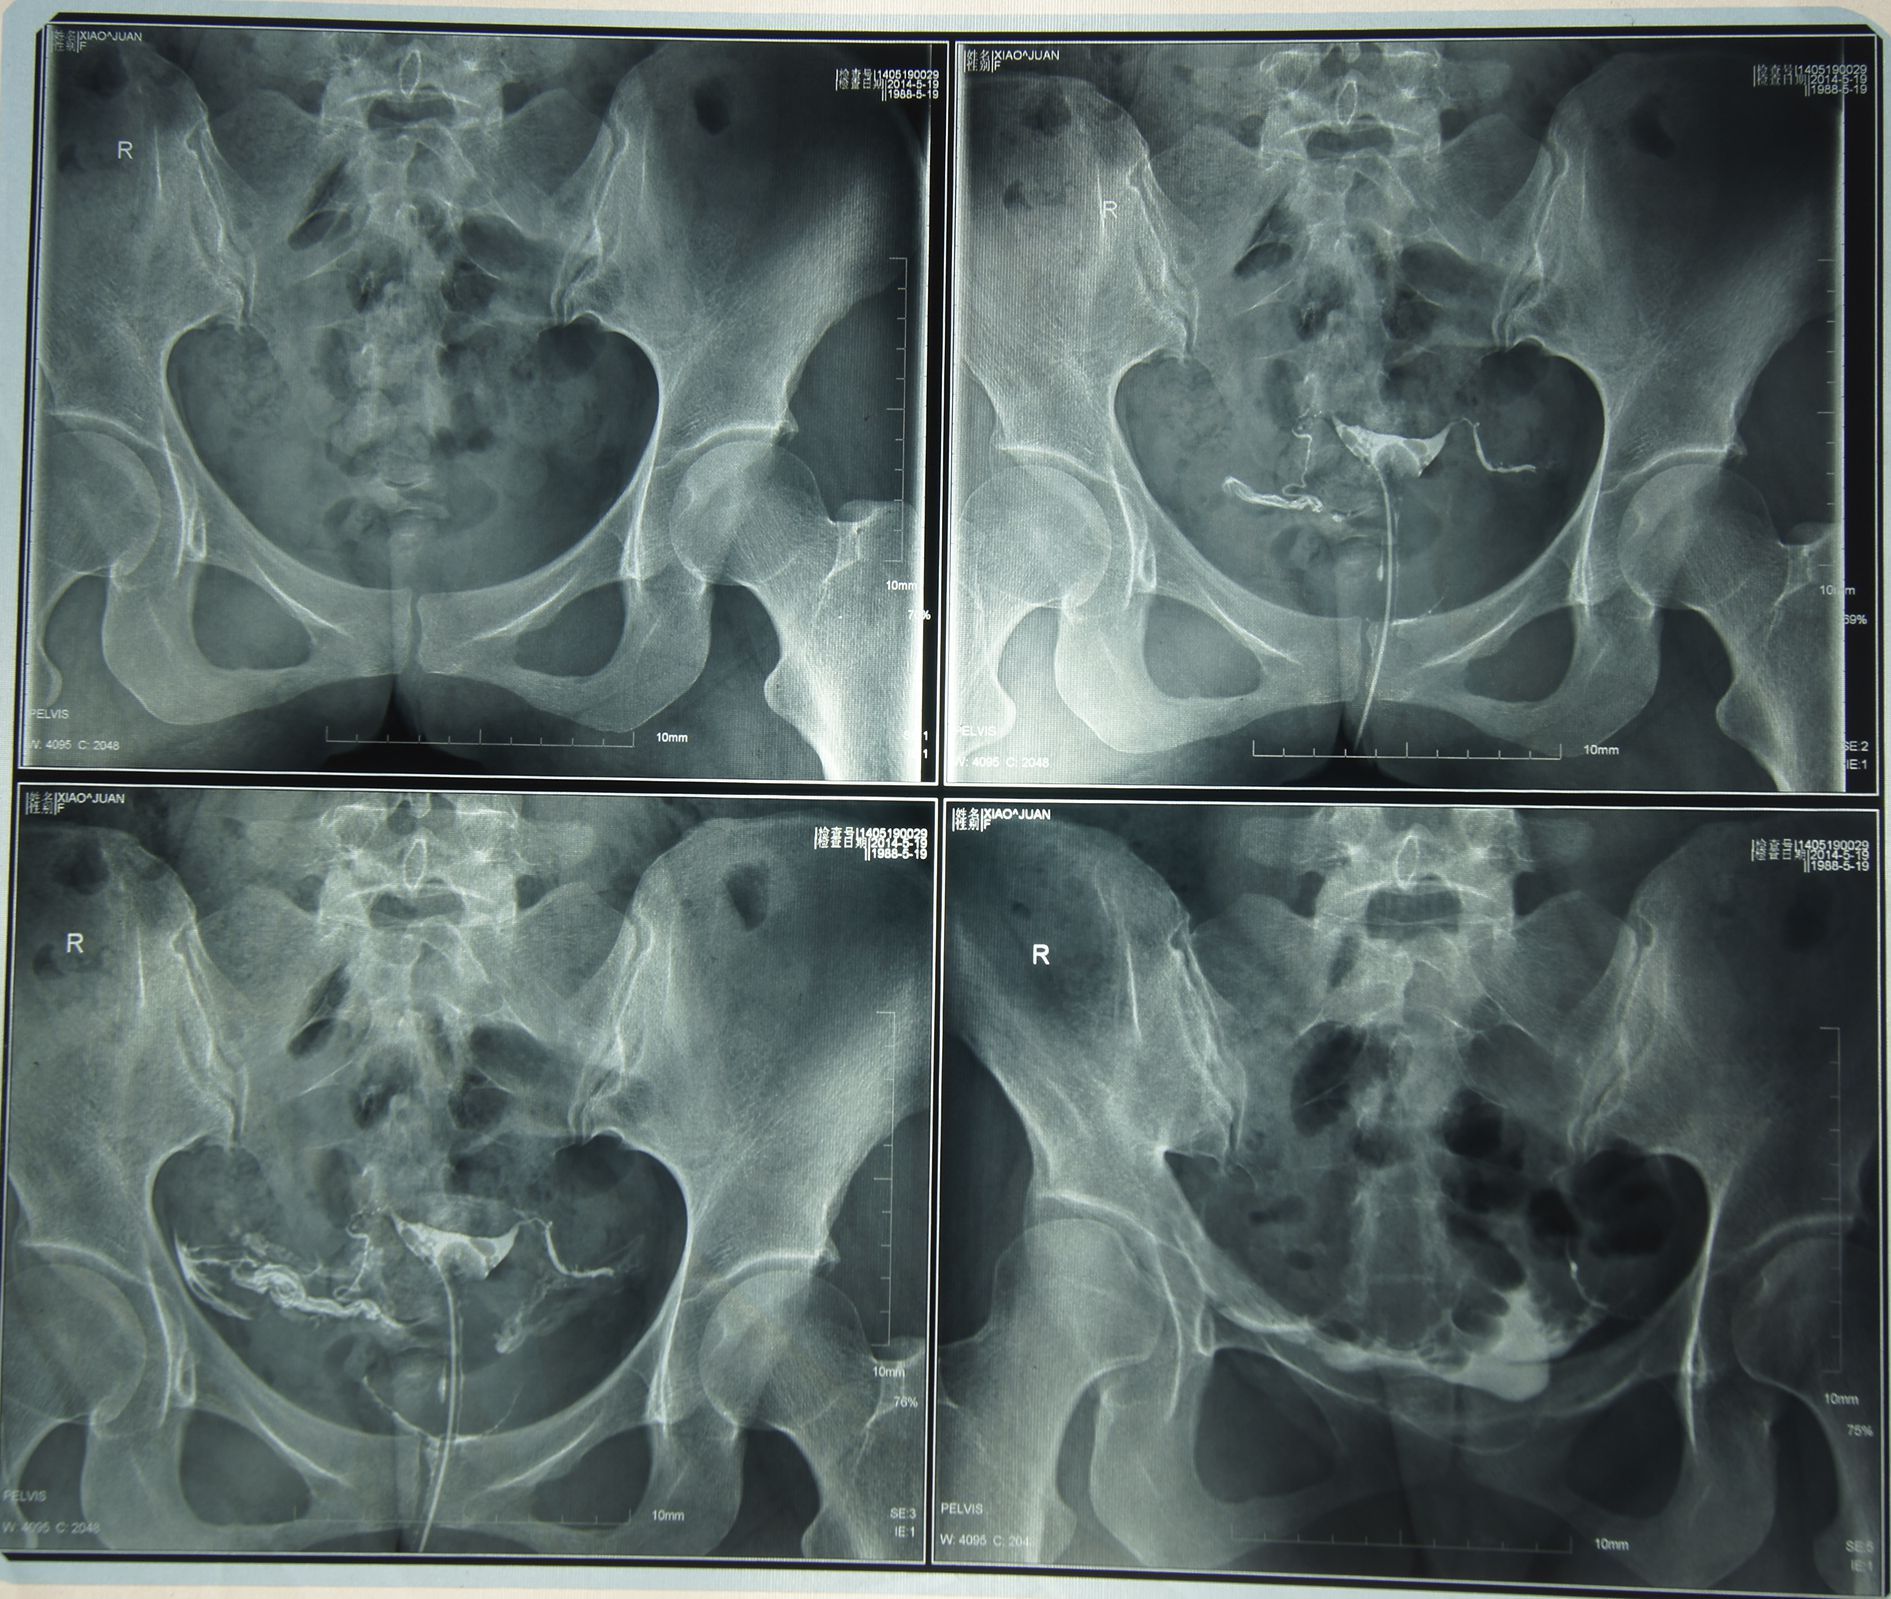

因为宫外孕,所拍了这个造影,医生讲的我还是不懂,说要我做试管婴儿,求求高师指点